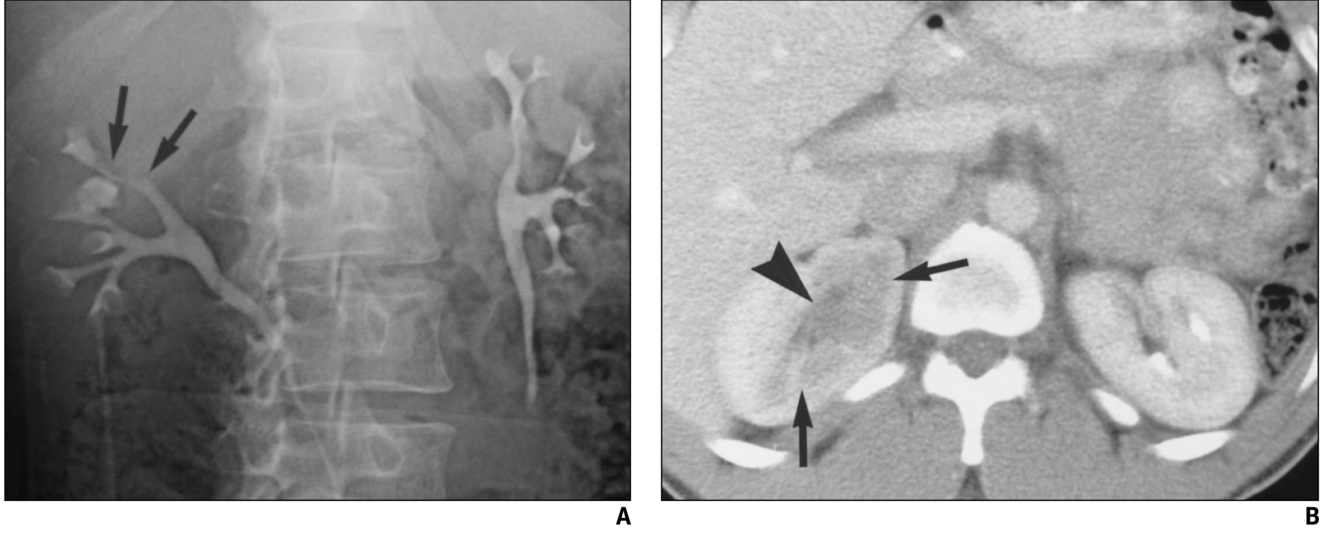

A 47-year-old male with right flank pain. (a) A magnified view from a control film of an intravenous urogram (IVU) demonstrates a 2 cm opacity in the right upper quadrant (arrow). This image clearly shows that the opacity is made up of multiple tiny calculi rather than a single large calculus, which should raise the suspicion that they lie within a calyceal diverticulum. (b) An oblique radiograph from a retrograde pyelogram study elegantly depicts the short, narrow infundibulum of a calyceal diverticulum arising from a mid-pole calyx (arrow).